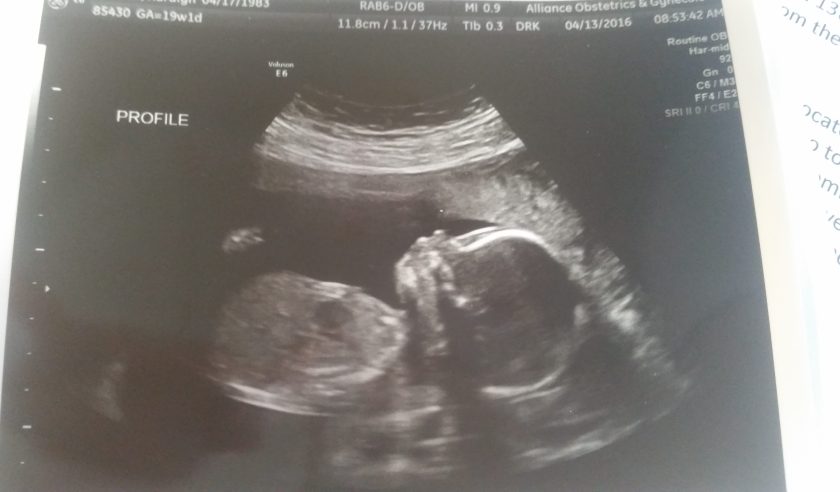

When we entered 2016, I can honestly say I was the happiest I had been in my life. I was pregnant with our first child. I was going to be a mother and Andy was going to be a father. By Christmas, Andy and I would be a family of three with a beautiful baby. I was on top of the world; the prospects of the Year 2016 held unlimited happiness for us.

It was around 20 weeks that we found out our son had Down syndrome (Ds). I will be honest with you. Our first reaction was that of devastation. And of grief. (I am shaking my head. Yes, grief). We felt like our world had come crashing down on us. The future we were counting on was no longer the future we were going to get.

Unfortunately, with Ds comes an increased risk in medical issues. We learned early on that Jensen had a confirmed heart defect (VSD) and another potential heart defect (it turns out he had a total of 4). And after 30 weeks, unbeknownst to all of us, he very quickly developed fluid around his lungs and stomach (hydrops fetalis).